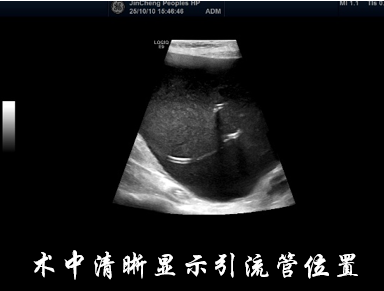

治疗第一步是穿刺引流减压。张奶奶取平卧位,医护人员对手术区域进行常规消毒铺巾后,用1%利多卡因进行局部麻醉。随后,在超声的实时引导下,将一次性8.5F PTCD引流管精准置入囊腔内,缓慢间断地引出囊液约2000ml,相当于4瓶矿泉水的量。引流结束后,张奶奶当即感觉腹痛、腹胀症状明显缓解,当天进食量就有所增加。